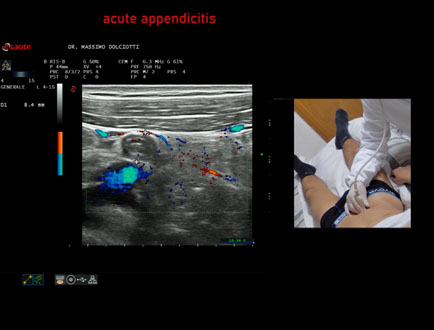

Data inserimento: 20/02/2026

Ecografia del: 13/02/2026

Strumento: Esaote MyLab Eight

Sonda: Lineare Multifrequenza 4-15 MHz

Età Paziente: M 22 anni

Motivazione dell'esame: da un giorno dolori addominali in sede ileo-cecale.

Commento all'esame: le immagini ed il video documentano, in sede ileo-cecale, appendice di spessore aumentato (9 - 10 mm - V.N. inferiore a 6 mm) con incremento della vascolarizzazione. Gli elementi ecografici segnalati orientano per appendicite acuta.

Conclusioni: appendicite acuta (acute appendicitis).

In collaborazione: Dr.ssa Marica Manfredi - Ancona, Dr. Ilir Qose - Ancona

Presentazione: Dr. Massimo Dolciotti - Ancona

Elaborazione digitale: Andrea Dini - Ancona